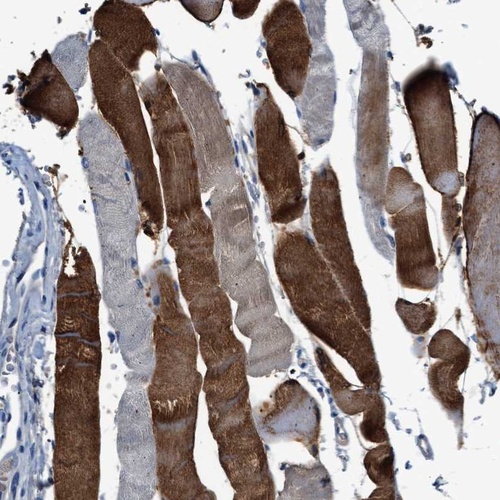

Immunohistochemical staining of human skeletal muscle shows strong cytoplasmic positivity in a heterogeneous staining pattern.